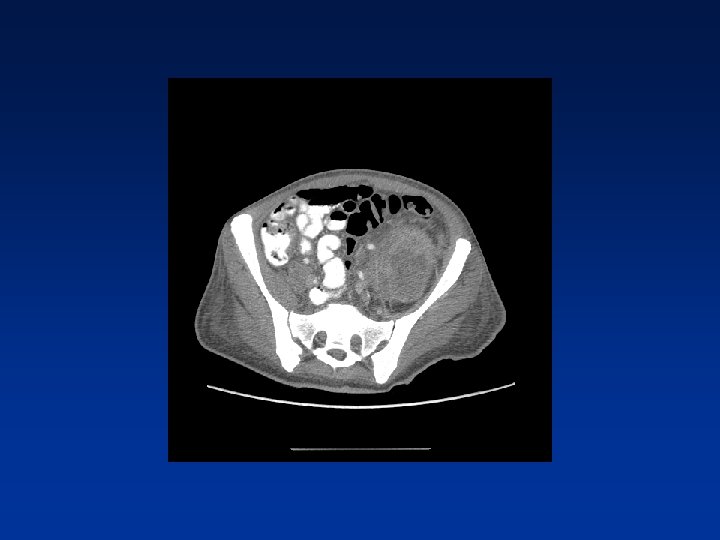

CASE